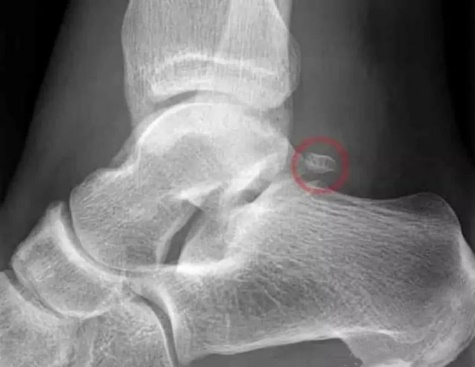

---X线片检查

主要判断关节位置以及有无明显骨赘增生。

(X线片检查可见后踝部位出现骨赘增生,在踝关节跖屈位会出现后踝的撞击)